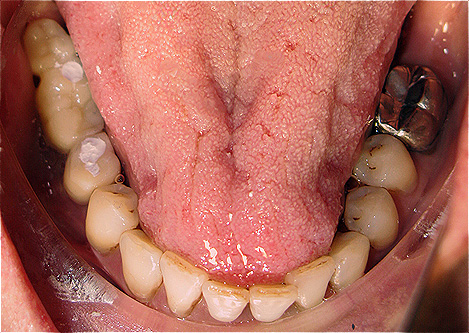

Resultado de colocação de implante dentário na Clínica São Filinto

Caso 1 - Implante imediato após extração do dente fraturado (dente 11) e implante imediato

![]() |